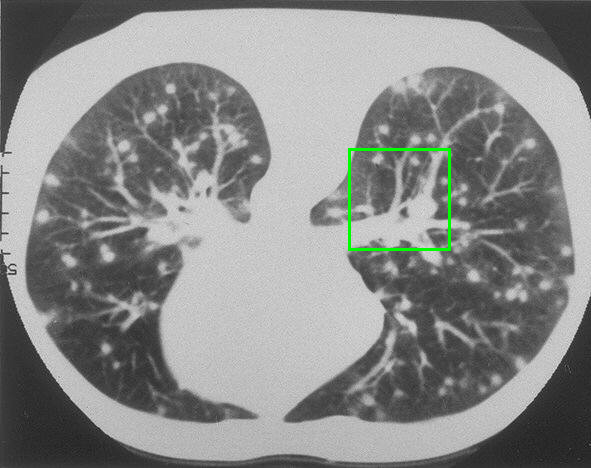

Example 2: restoration of images corrupted by blur and SPN or AWLN. In this example we evaluate the performance of the proposed TV-L1 model on three medical test images lungs (), Fig. 5 (a), ecography (), Fig. 6 (a), and aneurism (), Fig. 7 (a), synthetically corrupted by Gaussian blur of parameters band=5 and sigma=1 and by two types of impulsive noise, namely SPN and AWLN.

![]() |

| (a) original | (b) TV-L1 (ISNR = 11.04) | (c) zoom of (b) |

| (d) corrupted | (e) TVp-L1 (ISNR = 12.48) | (f) zoom of (e) |

| (g) -map () | (h) TV-L1 (ISNR = 15.30) | (i) zoom of (h) |

| (l) -map () | (m) TV-L1 (ISNR = 16.56) | (n) zoom of (m) |

First, for what concerns corruptions by SPN, in Figs. 5, 6, 7 we report for the three considered test images the original and corrupted image together with the estimated -maps in the first column (with the size of the neighborhoods used for the -maps estimation reported in the captions), the restoration results, obtained by the four compared methods, in the second column (with the achieved ISNR values in the captions) and a zoomed detail of the restored images - green- bordered in Figs. 5 (a), 6 (a), 7 (a) - in the last column.

The reported ISNR values as well as the visual inspection of the restored images and of the zoomed details strongly indicate how the proposed space-variant regularizer allows for higher quality restorations. In particular, it is worth remarking how, with respect to the space-variant TV model, the additional degrees of freedom represented by the scale parameters used in our proposal, yield a sufficient additional flexibility for avoiding unwanted spurious effects - see, e.g., spikes in Figs. 5 (i), 6 (i), 7 (i).